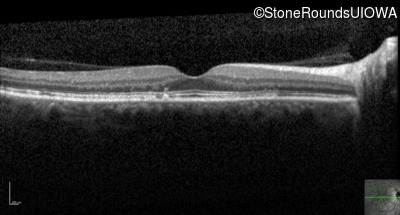

Optical Coherence Tomography - Right - 20/20

Exemplar / OCT Stack

Optical Coherence Tomography - Left - 20/20 -1